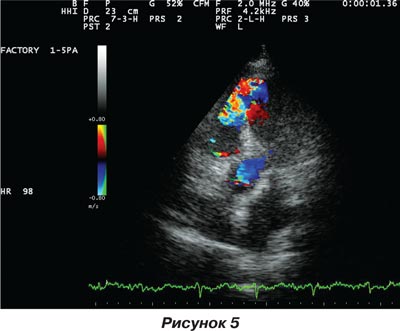

При ЭхоКГ выявлен обширный дефект межжелудочковой перегородки, сопровождающийся массивным потоком из левого в правый желудочек сердца с развитием выраженной легочной гипертензии, что и явилось причиной развития кардиогенного шока (рис. 4, 5).